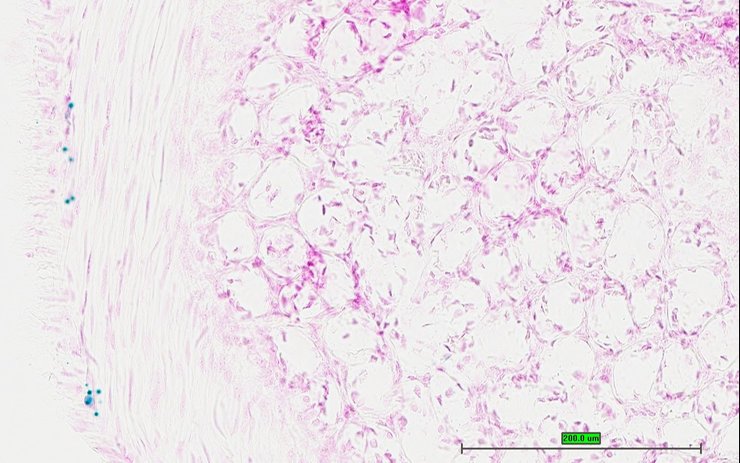

TS28: epididymis Present UC Davis_1879397

Specimen UC Davis_1879398: postnatal adult; Cnga3tm1.1(KOMP)Vlcg/Cnga3+ (more )

TS28: ductus deferens Present UC Davis_1879398 vas deferens

Contributing Projects: